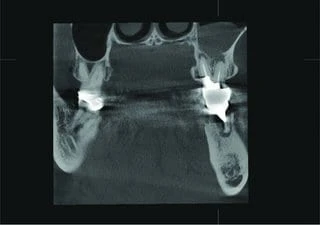

The patient presented with an unclear situation around tooth 26, which had undergone endodontic treatment before. Conventional 2D X-rays did not allow a conclusive diagnosis; therefore, a 3D scan was performed with Veraviewepocs 3D R100. The sagittal and coronal view showed that the endodontic treatment had not been successful and that there were apical defects on the buccal and palatal root.

The sagittal view clearly confirms perforation of the Schneiderian membrane, and the coronal view revealed an odontogenic maxillary sinusitis and pachymenia. The injury of the sinus membrane may have been overlooked in this case if the diagnosis had been formulated on the basis of an X-ray that did not show the problem so clearly.